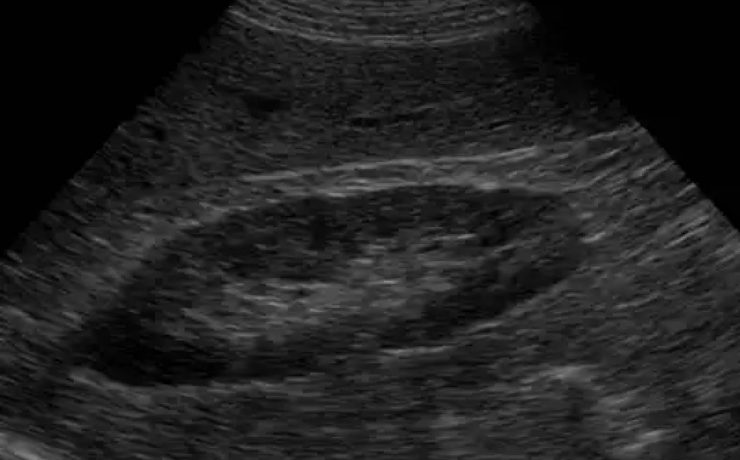

EL MODO A (modo de amplitud) fue el primer método utilizado para formar imágenes de ultrasonido. EL MODO B: modo de brillantez MODO M: modo de movimiento. Tiene su utilidad principal en ecocardiografía tanto en la fetal como en la del adulto. MODO B.- imagen en tiempo real. Al mover